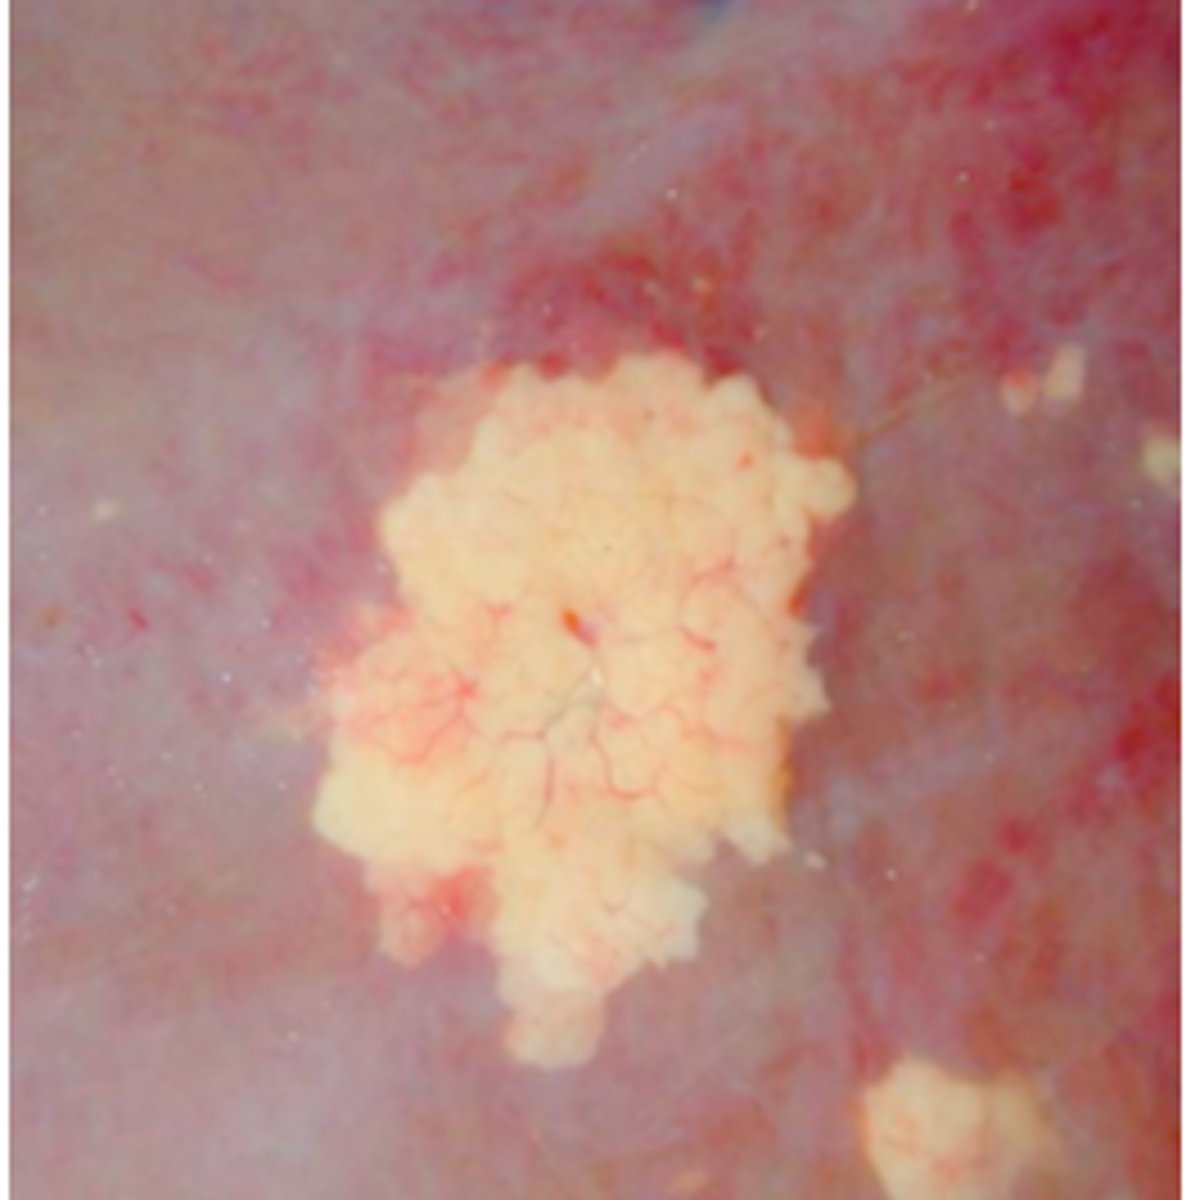

Kronisk peritoneal og perihepatisk cystecerkose

Ætiologi: Cysticerus tenuicollis

Lever fra får (med diaphragma, D), hvad er den patoanatomiske diagnose og ætiologien?